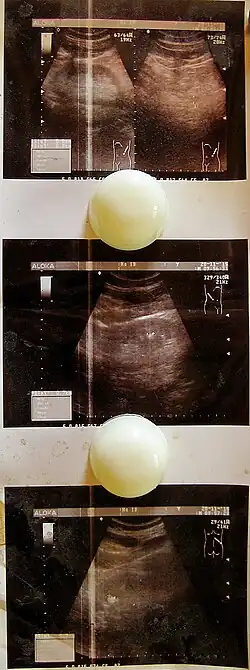

- УЗИ мочеполовых органов, позволяющее исключить сопутствующие заболевания;